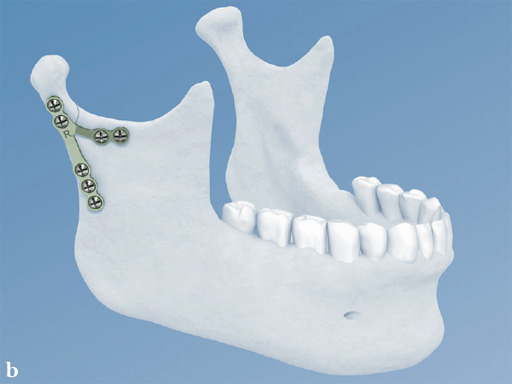

Lambda Plate

The lambda plate comes in a left and right version. It emulates a two-plate technique as its specific shape and 7-hole design with the width of a single plate at the top segment allows the surgeon to advance the lambda plate high up into the very narrow zone of the condylar neck just below the head. The fixation arms straddle the mandibular canal to avoid injury risk of the inferior alveolar nerve.

The lambda plate can be placed using retromandibular or submandibular surgical approaches. For positioning, the straight 5-hole segment is placed parallel to the posterior ramus border aligned with the condylar head. If required the anterior arm may be bent to fit the bony surface below the sigmoid notch.